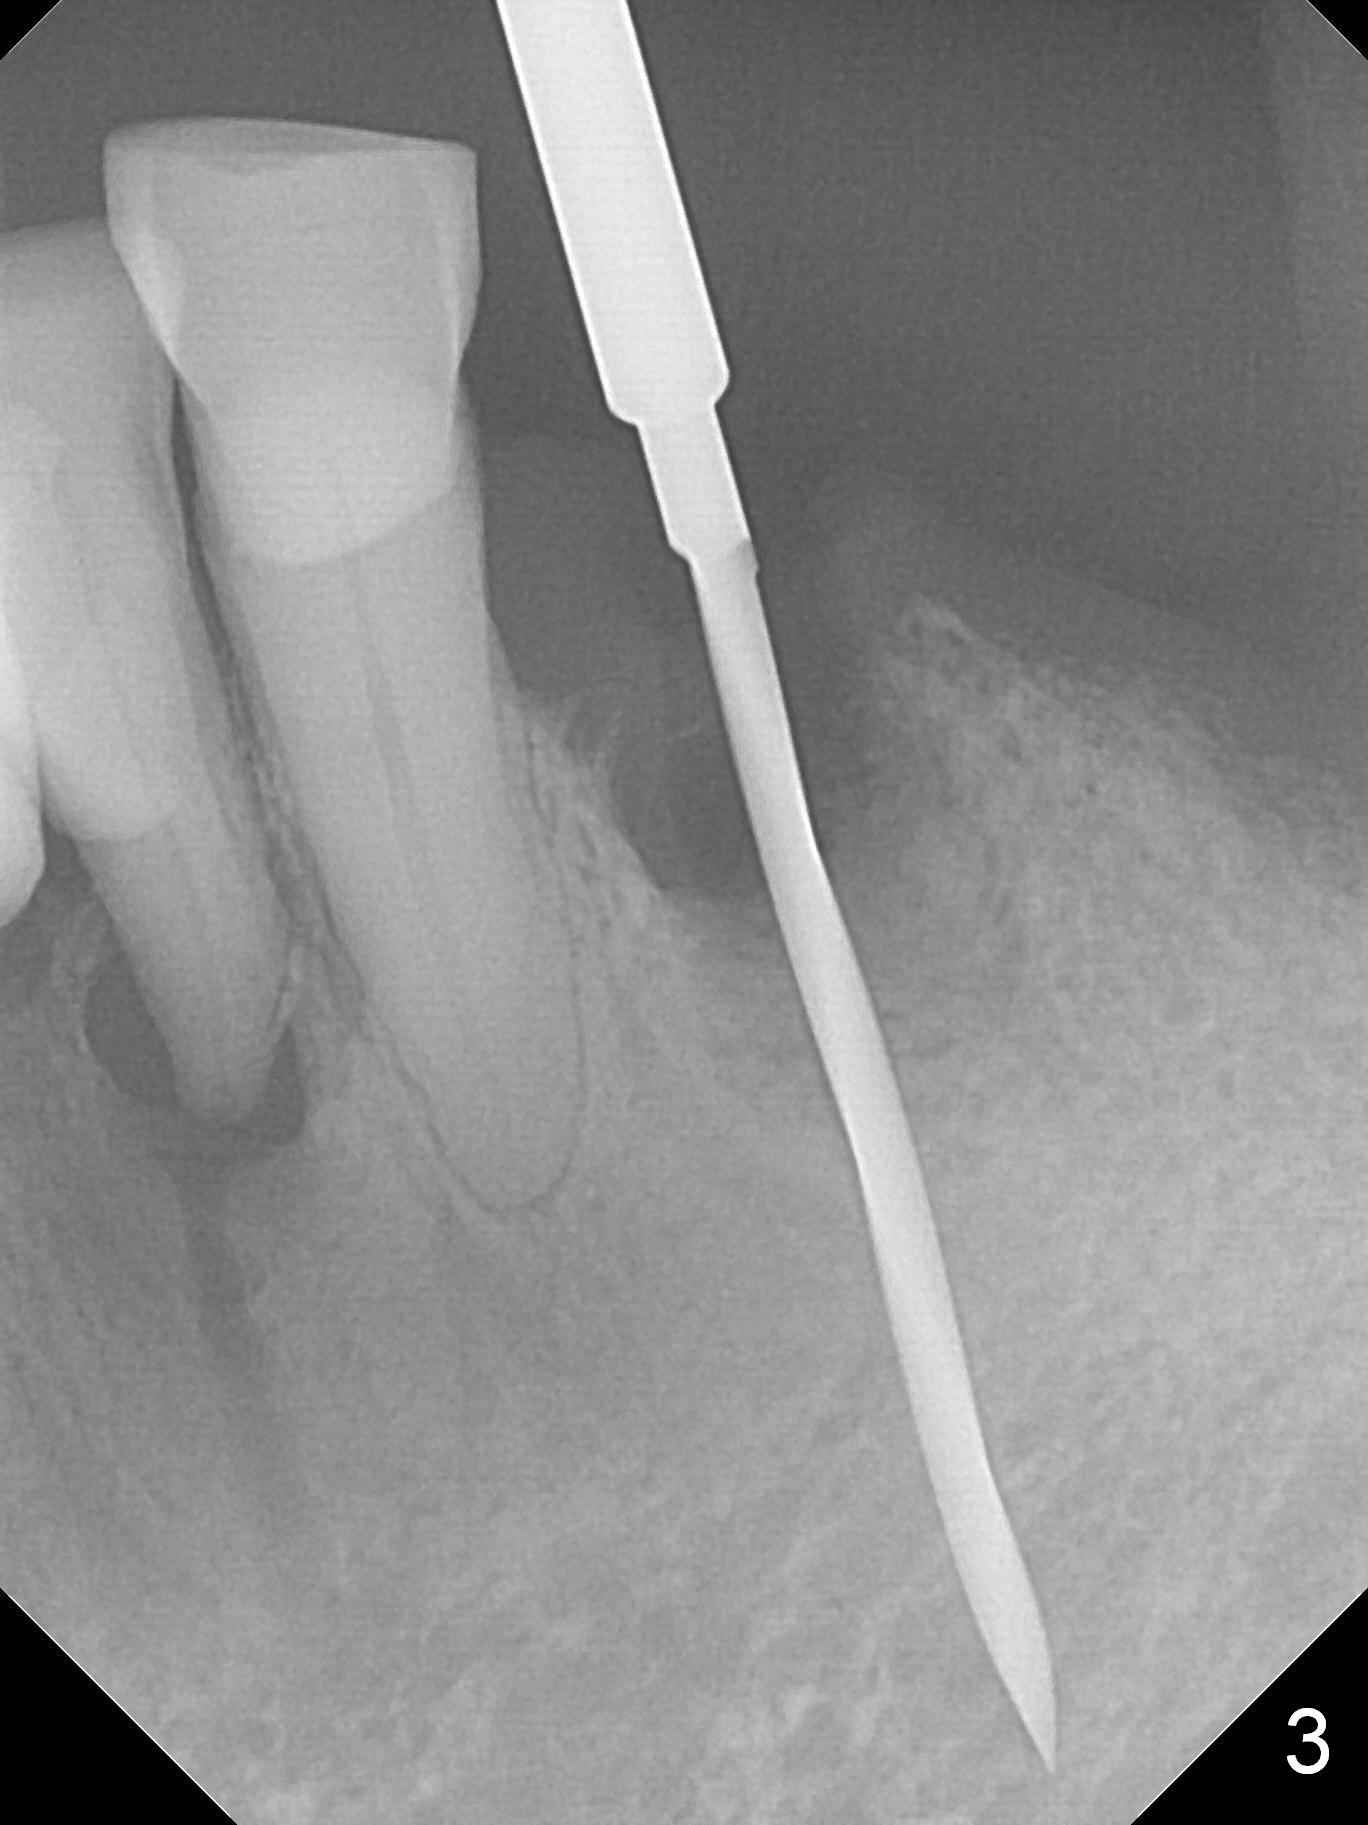

A 72-year-old man presents to clinic for implants because of pain associated with wearing the lower partial. The teeth #21, 24, 25 and 31 seem to be non-salvageable and are going to be replaced by implants so that the lower RPD can be reused (Fig.1). The edentulous ridge is atrophic (Fig.9 *). The upper complete denture appears to be functional. Since the tooth #21 is symptomatic (Fig.2) and the patient has chronic TMJ dislocation, the affected tooth is extracted first (Without antibiotic socket treatment) for immediate implant (Fig.3 (1.5 mm drill (placed more lingually)). The lower RPD is used as a surgical guide (Fig.4 (3 mm drill in place)). When a 3.8x16 mm implant is placed with bone graft (Fig.5 *), the underlying neurovascular bundle is undetected. A small field of panoramic X-ray is retaken; it seems that there is enough clearance from the Mental Foramen (Fig.2,6,7 (red dashed line)) and the Incisive Canal (pink dashed line). The implant is then placed 2 mm more apically (Fig.7) to reduce the chance of periimplantitis since the buccal plate is lost. A 5.5x5(5) mm abutment is placed (Fig.5) with more graft. The access of the abutment is left open so that a part of periodontal dressing is inserted for additional retention (Fig.8,9). The RPD is placed back for adaptation of the dressing. The patient is advised not to wear the RPD postop to reduce micromovement.